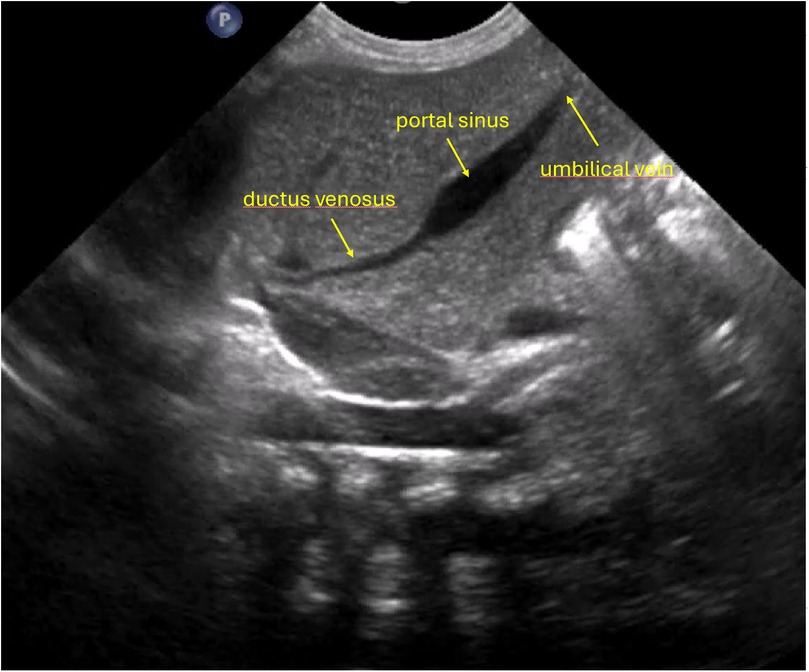

Figure 2

Ultrasound image showing newborn anatomy with labeled structures.

Figure 2. Anatomical configuration in which the ductus venosus arises at a sharp angle and/or presents a narrower lumen, potentially increasing the technical complexity of catheter advancement.